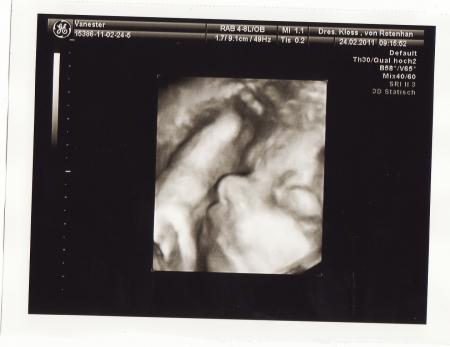

Soo nun kann ich mein kleinen auch endlich mal sehen wie er aussieht.. und er ist so süß.. sieht genauso aus wie mein großer nur leider habe ich bei mein großen nur 1 bildchen, weil er sich nicht zeigen wollte.. Naja bei diesen Baby ist es nicht anders aber naja seht selbst.. Denke es gibt besser 3D Bilder aber dafür das er auch fotoscheu ist sind die ganz niedliche geworden.. Achso und statt 75euro bezahle ich nur 50 euro.. Lg Britta

Bild zu Soo 3D bilder abgeholt... - Forum für April - Mamis